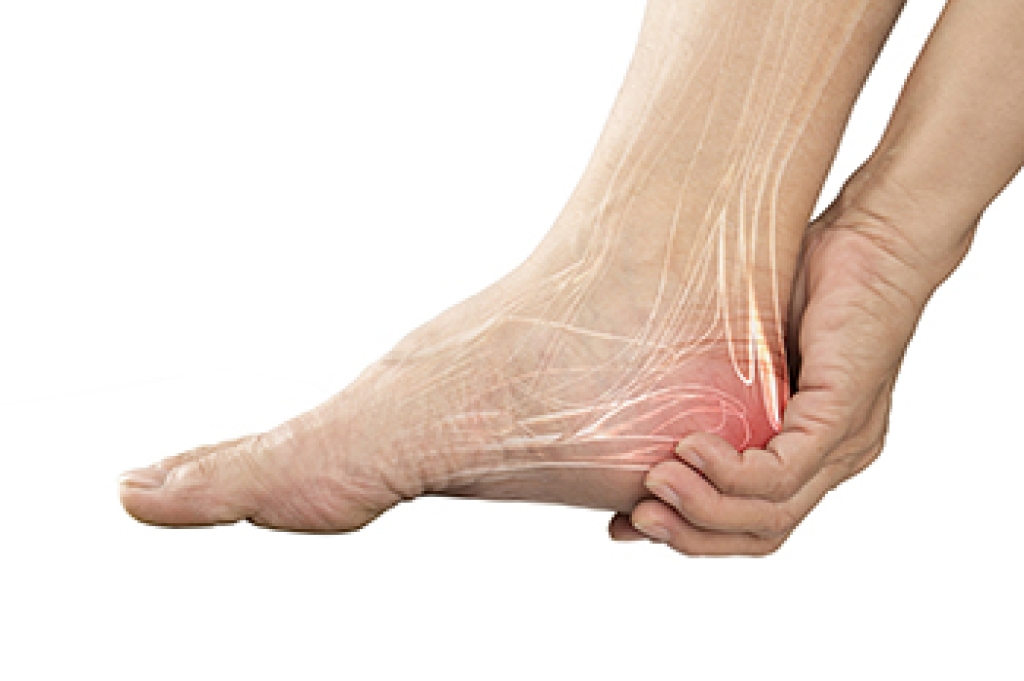

A bruised heel, also known as a heel contusion, occurs when the fat pad under your heel becomes damaged from repeated impact or a hard landing. Common causes include running on hard surfaces, jumping sports, or wearing shoes that lack proper support. It typically feels like a deep, dull ache or tenderness directly under the heel, especially when standing or walking. In contrast, a broken heel, or heel bone fracture, is much more severe, and often results from a traumatic injury like a fall from height or a car accident. Symptoms include intense pain, swelling, bruising, and difficulty bearing weight. Both conditions can make walking painful, but a broken heel usually requires more intensive treatment and a longer recovery period. A podiatrist can perform a physical exam and imaging tests to determine the cause of your heel pain and develop a personalized treatment plan that may include rest, orthotics, or targeted exercises. If you have heel pain, it is suggested that you schedule an appointment with a podiatrist.

Heel pain is often associated with plantar fasciitis. The plantar fascia is a band of tissues that extends along the bottom of the foot. A rip or tear in this ligament can cause inflammation of the tissue.

Achilles tendonitis is another cause of heel pain. Inflammation of the Achilles tendon will cause pain from fractures and muscle tearing. Lack of flexibility is also another symptom.

Heel spurs are another cause of pain. When the tissues of the plantar fascia undergo a great deal of stress, it can lead to ligament separation from the heel bone, causing heel spurs.

Heel pain should be treated as soon as possible for immediate results. Keeping your feet in a stress-free environment will help. If you suffer from Achilles tendonitis or plantar fasciitis, applying ice will reduce the swelling. Stretching before an exercise like running will help the muscles. Using all these tips will help make heel pain a condition of the past.